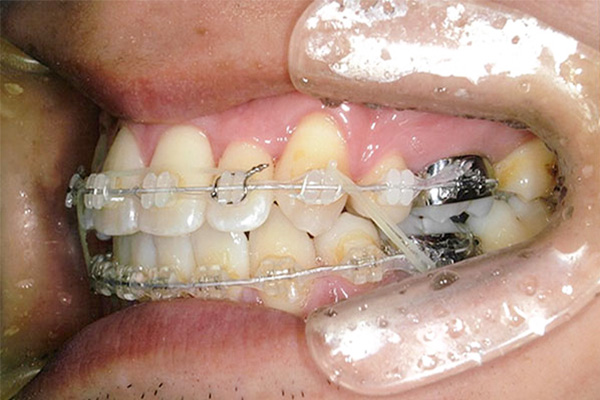

症状八重歯+二重歯列による噛み合わせ不具合

抜歯あり

1年後